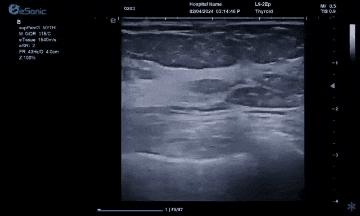

银河官网医疗(ESI)设计的原数精准准台式平台,采用软声束成像系统,采集帧频达到10000Hz/S,每秒处理数据达10亿次,这是超声历史上首次做到准台式机型使用超快速平台。使用此平台,加快了临床图像的帧频采集速度和屏幕显示的刷新速度,获得更加清晰的图像,对女性两腺较细小病灶有较高的细微结构分辨率,有助于增强诊断和治疗决策的信心。

借助更高水平的图像清晰度有助于临床医生更早的发现两腺疾病,这将对患者的治疗机会和整体健康状况产生重大影响。借助经过验证的、接受时间考验的人工智能驱动应用程序和简化检查的先进自动化功能,我们正在提供有助于提高易用性和提高更清晰图像的技术,帮助医生更快的完成更加苛刻的工作流程,同时提供更高的一致性和准确性,最终帮助患者获得更好的健康结果。